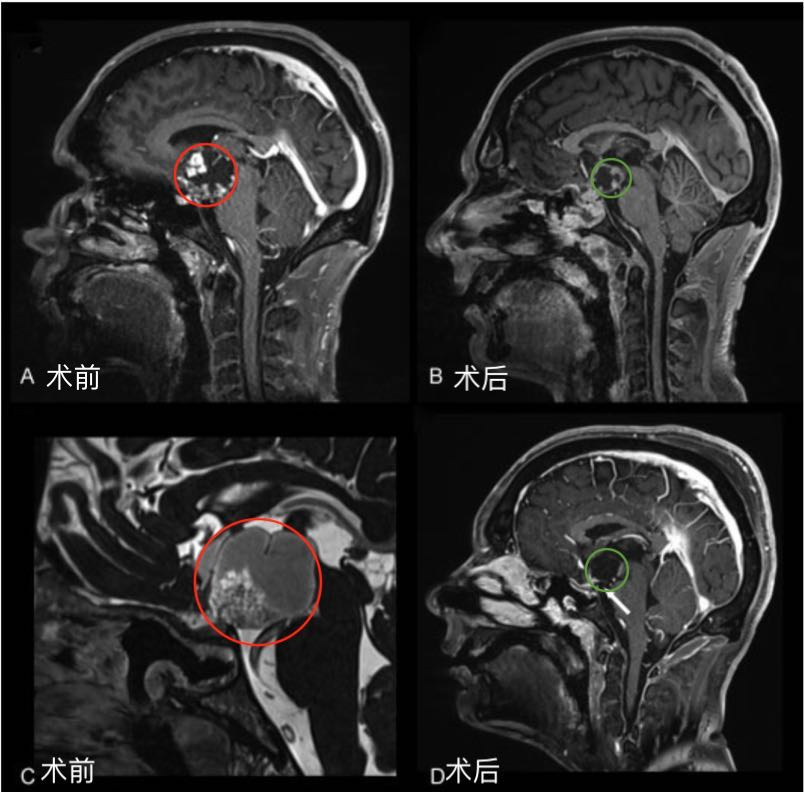

【颅咽管瘤赴德手术案例】颅咽管瘤三次手术后反复发作,赴德手术终获全切,术后半年未复发。经历了千辛万苦的治疗,却又功亏一篑肿瘤复发,对于任...

18岁小杰,本该青春正好的年纪,他却饱受颅咽管瘤折磨,10多年内三次手术、四次复发。所幸,他较后找到INC德国巴特朗菲教授全切脑瘤,术后的他恢复状...

颅咽管瘤手术治疗有多种手术入路,入路的选择应根据肿瘤的大小、生长部位、肿瘤的钙化程度、接近脑脊液通路的便利程度来决定。小杰的主刀医生INC巴...